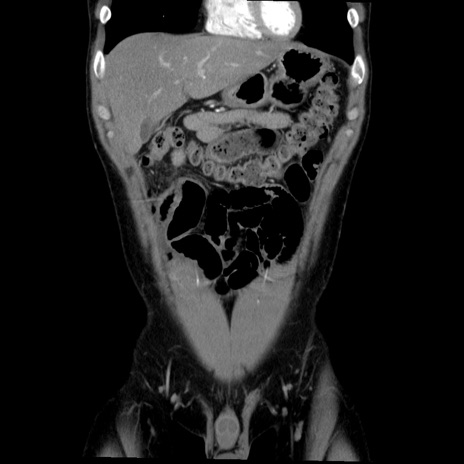

症例36(冠状断像)

【症例】20歳代 男性

【主訴】心窩部痛

【現病歴】今朝より上腹部痛あり。一旦軽快していたが再度出現したため救急要請。昨日夕に白身の魚を含む刺身を食べた。

【身体所見】BP 136/89mmHg、HR 74/min、BT 37.0℃、腹部:膨満、軟、心窩部に圧痛あり。反跳痛なし、筋性防御なし、腸雑音やや亢進あり。

【データ】WBC 17700、CRP 0.48